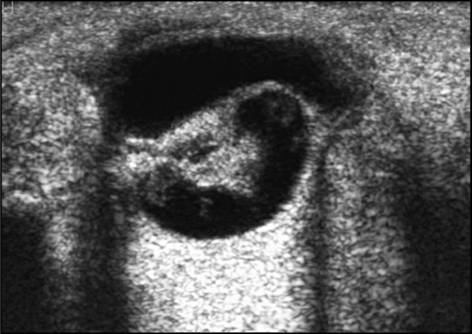

УЗИ: отслойка сетчатки может быть неполной

(частичной) и полной (тотальной). Частично отслоенная сетчатка имеет вид четкой

эхоген-ной полоски, располагающейся у заднего полюса глаза и параллельно его

оболочкам.

Субтотальная отслойка сетчатки может быть в виде

плоской линии или в форме воронки; тотальная, как правило, воронкообразная или

Т-образная. Она расположена не у заднего полюса глаза, а ближе к его экватору

(отслойка может достигать 18 мм и более), поперек глазного яблока (рис. 13).

Воронкообразная отслойка сетчатки имеет типичную

форму в виде латинской буквы V с местом прикрепления у диска зрительного нерва

(см. рис. 13).

Рис. 13. Эхограммы глазного яблока: а)

субтотальная отслойка сетчатки; б) тотальная (воронкообразная) отслойка

сетчатки